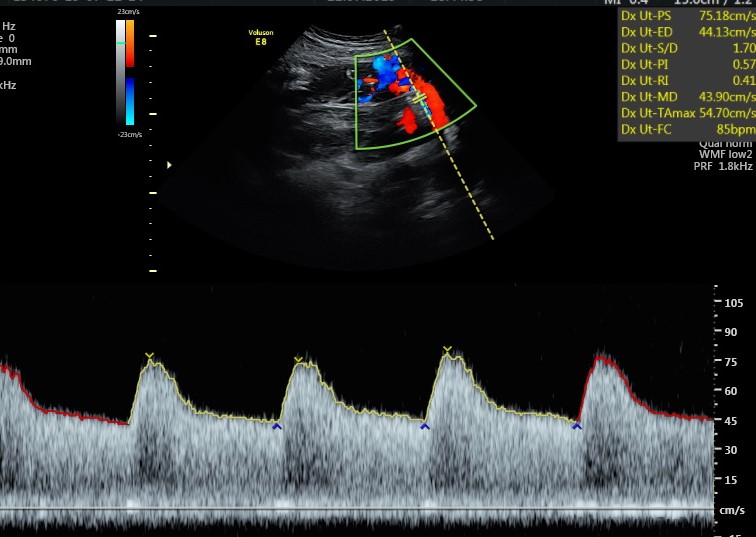

A livello ecografico non ci sono particolari controlli da fare, se non quello della arterie uterine se all’ecografia morfologica erano ancora un po’ vasocostrette.

Infatti la placenta in questo mese e mese e mezzo ha continuato la sua opera di modificazione delle arterie uterine per renderle dei vasi a bassa resistenza e conseguentemente assicurandosi un buon apporto di sangue per il resto della gravidanza. Se anche in questa occasione le arterie uterine dovessero ancora avere le resistenze aumentate è importante pianificare una ecografia di accrescimento ogni mese e monitorare la pressione della mamma su base quotidiana.